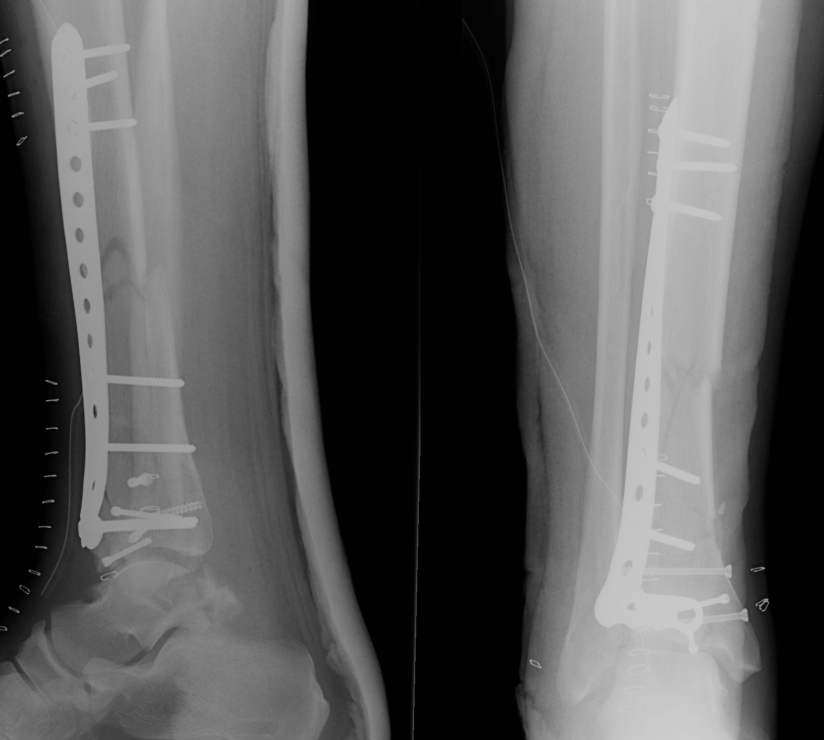

Tibial Plafond Pre External Fixator APTibial Plafond Pre External Fixator LateralTibial Plafond Post External Fixator APTibial Plafond Post External Fixator Lateral

Tibial Plafond CT AxialTibial Plafond CT SagittalPlafondTibial Plafond ORIF APTibial Plafond ORIF Lateral